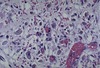

A

- bacterial endocarditis

- blue smudges = inflammatory cells or bacteria

- lighter pink = fibrin

- darker pink = collagen